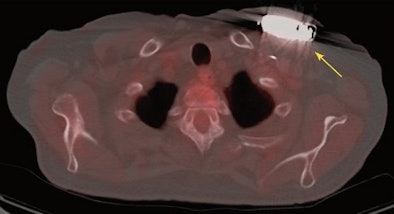

![]() |

| Fused PET/CT image shows abnormal FDG uptake (yellow arrow) posterior to the IED generator and compatible with infection. Image courtesy of JACC. |

Upon review of the images in group A, 32 (76%) of the 42 patients with suspected CIED infection exhibited positive FDG-PET/CT results. Abnormal FDG uptake around the device generators was seen in 18 patients (43%), and 18 individuals also had uptake over the leads. Thirteen patients (31%) had abnormal uptake in the superficial skin tissue, 13 in the subcutaneous tissue, and two (5%) within the heart.

The researchers defined positive FDG-PET/CT results as abnormal FDG uptake near the generator pocket and/or along the cardiovascular IED at the generator or the leads. They noted the areas of abnormal FDG uptake and categorized them according to the following regions: skin, subcutaneous tissue, surrounding area of generator, overlying leads, and intravascular/intracardiac.